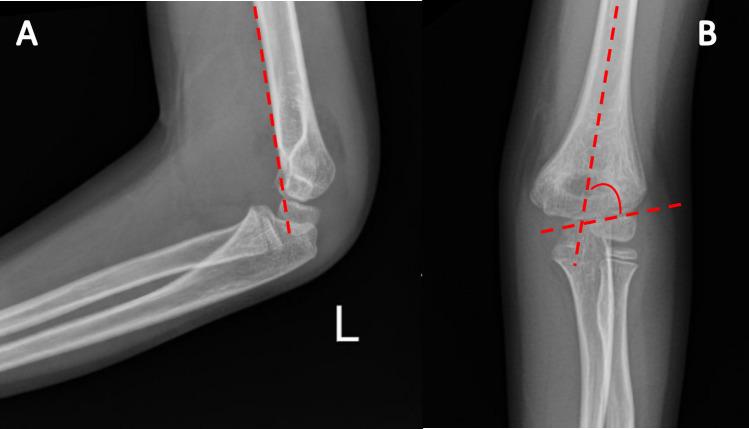

Supracondylar humeral fractures (SCF) are one of the most common traumatic fractures in pediatric populations, characterized as transverse fractures at the distal humerus between the medial and lateral columns. Early studies strongly opposed closed reduction and casting as an acceptable treatment modality for Gartland type II fractures as an early case series showed high rates of complications; however, more recent studies have suggested better outcomes. The optimal management of Gartland Type II supracondylar fractures has yet to be fully elucidated. This review highlights the indications, complications, and outcomes of nonoperative Gartland Type II supracondylar humeral fracture management. Additionally, it demonstrates the need for further research to inform guidelines on managing this condition.

肱骨髁上骨折(SCF)是小儿人群中最常见的创伤性骨折之一,其特征为肱骨远端内侧柱和外侧柱之间的横行骨折。早期研究强烈反对将闭合复位和石膏固定作为Gartland II型骨折可接受的治疗方式,因为一个早期病例系列显示并发症发生率很高;然而,最近的研究表明结果更好。Gartland II型髁上骨折的最佳治疗方法尚未完全阐明。本综述重点介绍了Gartland II型肱骨髁上骨折非手术治疗的适应症、并发症和结果。此外,它表明需要进一步研究以为管理这种情况的指南提供依据。